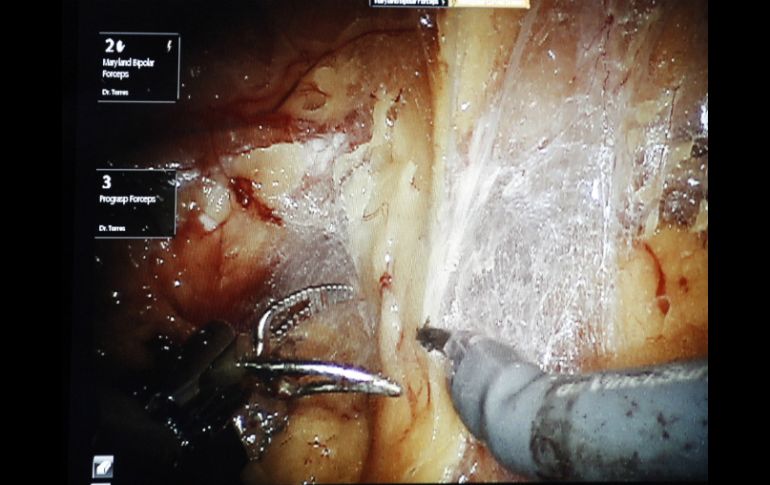

Tecnología | La máquina realizó el procedimiento en animales sin que un médico lo manejara Robot sutura tejido por sí mismo La máquina realizó el procedimiento en animales sin que un médico lo manejara Por: NTX 4 de mayo de 2016 - 19:05 hs El dispositivo para 'suturar tejido' cuenta con brazos que llegan a las aberturas más pequeñas en el cuerpo. NTX / ARCHIVO WASHINGTON, ESTADOS UNIDOS (04/MAY/2016).- Ser suturado por el doctor Robot podría ser realidad algún día: los científicos han creado un sistema robótico que realizó justo eso en animales vivos sin que un médico lo manejara. En forma muy similar a los ingenieros que están diseñando vehículos autónomos, la investigación mostrada el miércoles forma parte de un movimiento hacia la creación de robots quirúrgicos autónomos, con lo que se prescinde de las manos del cirujano en ciertas tareas que una máquina podría realizar completamente por sí misma. No, los médicos no se apartarían del paciente: se supone que deben supervisar, y ellos realizarían el resto de la cirugía. Y el dispositivo tampoco está listo para las salas de operaciones. Pero en pruebas pequeñas con cerdos, el brazo robótico realizó sutura de tejido intestinal tan bien, y en algunos casos incluso un poco mejor, que algunos cirujanos que compitieron con el dispositivo, reportaron investigadores en la revista Science Translational Medicine. "El propósito no era reemplazar a cirujanos", dijo el doctor Peter C. W. Kim, del hospital Children's National Health System en Washington, un cirujano pediatra que encabezó el proyecto. "Si se tiene una herramienta inteligente que trabaja con un cirujano, ¿puede mejorar el resultado? Eso es lo que hemos hecho". Si usted ha escuchado sobre máquinas como el popular sistema Da Vinci, podría pensar que los robots ya están operando. No realmente. En la actualidad muchos hospitales ofrecen cirugías asistidas por robot en las que los cirujanos utilizan la maquinaria como herramienta que ellos controlan manualmente, usualmente para operar a través de aberturas pequeñas en el cuerpo. Pero la cirugía asistida por robot ha sido controversial, ya que algunos estudios han mostrado que puede generar mayores costos sin mejores resultados. Entonces, ¿por qué el esfuerzo por robots autónomos de nueva generación? Los que lo proponen piensan que existen casos en los que la precisión de una máquina puede superar a la de una mano humana. El proyecto presentado el miércoles es "el primer pequeño paso hacia la autonomía verdadera", dijo el doctor Umamaheswar Duvvuri, del Centro Médico de la Universidad de Pittsburgh, un cirujano de cabeza y cuello y especialista en robótica que no estuvo involucrado en el nuevo trabajo. Pero no esperen ver a los médicos dejar las operaciones completas en manos de un robot, advirtió. Debido a que está diseñado para realizar una tarea específica ”suturar tejido” la máquina es muy parecida a la tendencia de automatización en otras industrias. Brazos robóticos realizan la tarea de soldadura y pintura en la mayoría de las líneas de ensamblaje de automóviles en Estados Unidos. Temas Ciencia médica Robots Robótica Lee También ¿Cómo se forman los recuerdos en la mente? Julieta Fierro será homenajeada en la FIL INAPAM: ¿Cómo solicitar un turno para consulta médica gratuita? Nobel de Química premia el desarrollo de estructuras metal-orgánicas Recibe las últimas noticias en tu e-mail Todo lo que necesitas saber para comenzar tu día Registrarse implica aceptar los Términos y Condiciones